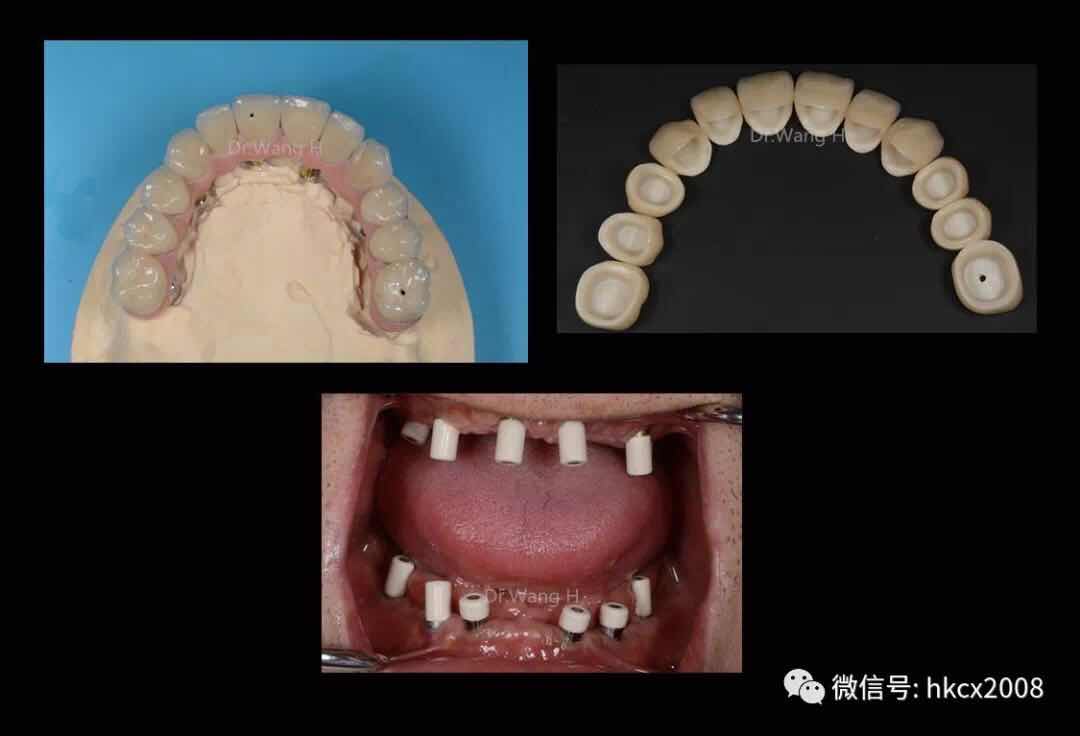

说这番话的是,来自福建的张老师,在杭州口腔医院城西院区特需专家科王辉主任团队402诊室顺利完成全口种植牙修复。